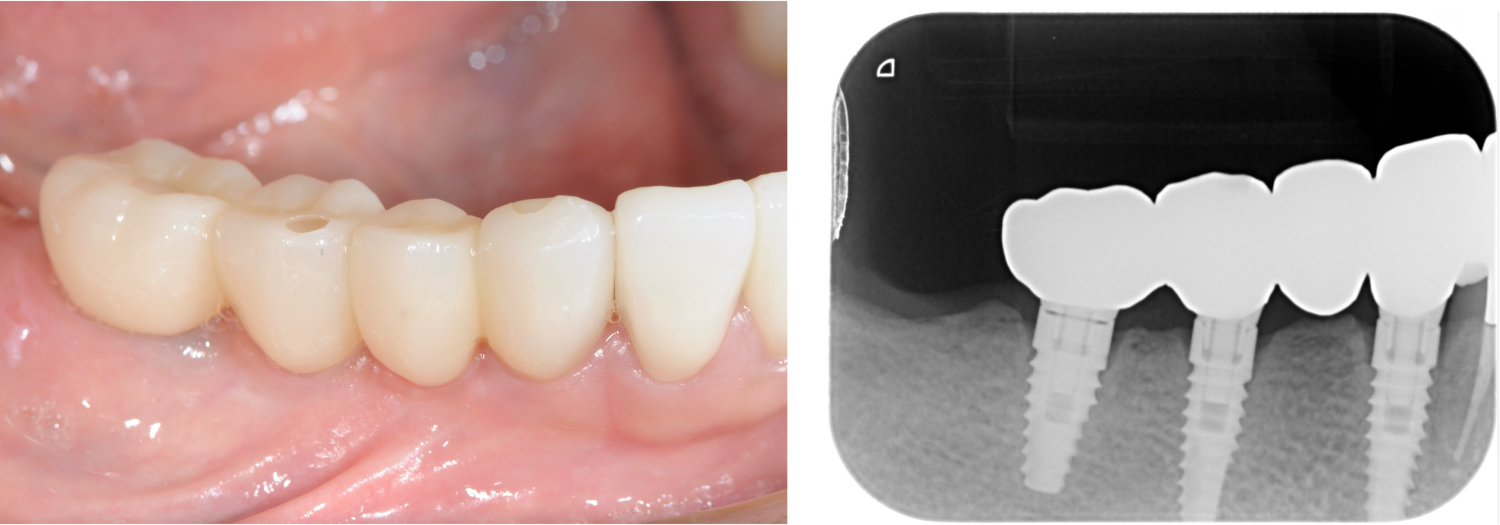

| 主訴 | 全顎治療希望、下の奥の歯が無いので全く噛めない。綺麗で噛めるようになりたい |

| 治療内容 | 下顎臼歯部欠損放置のため、臼歯部においてスペースがないため、全顎治療を行い咬合再構成を行う。 早期においてインプラント治療、咬合関係を模索した後、全顎にわたりセラミックによる補綴治療、その後メインテナンスに移行 |

| 治療費 | 5,410,000円(税込)(インプラントすべて含む) |

| 治療期間 | 1年8ヶ月 |

| 治療回数 | 80回 |

| 想定されたリスク | 食いしばり(パラファンクション)によるセラミックの破折、歯の破折 |